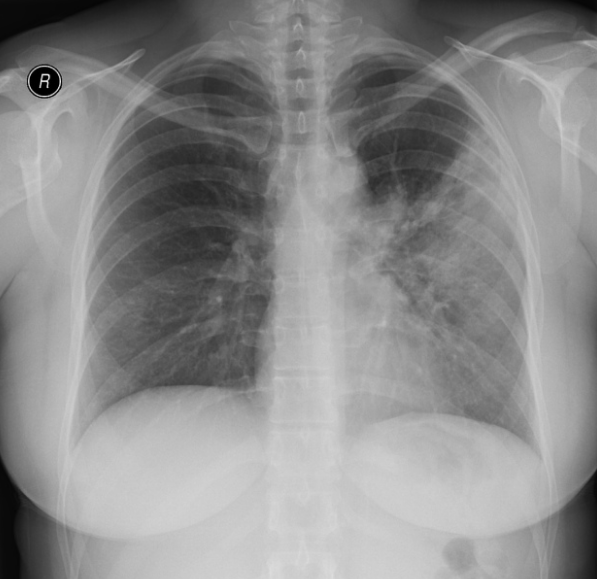

78세 여성이 발열, 호흡곤란, 그리고 가래 증상을 호소하며 내원하였다. 환자의 가슴 X선 사진이다. 이 환자의 폐 병변은 어디에 위치해 있는가?

발열과 호흡기증상이 있으며 CXR상 consolidation이 있어 폐렴이 의심된다. 좌측 폐에 병변이 있으며, lateral view에서 LUL임을 알 수 있다. Chest PA상 심장 좌측 경계가 불분명하게 관찰되므로 보기 중에서 병변의 위치를 LUL anterior segment로 짐작할 수 있다.